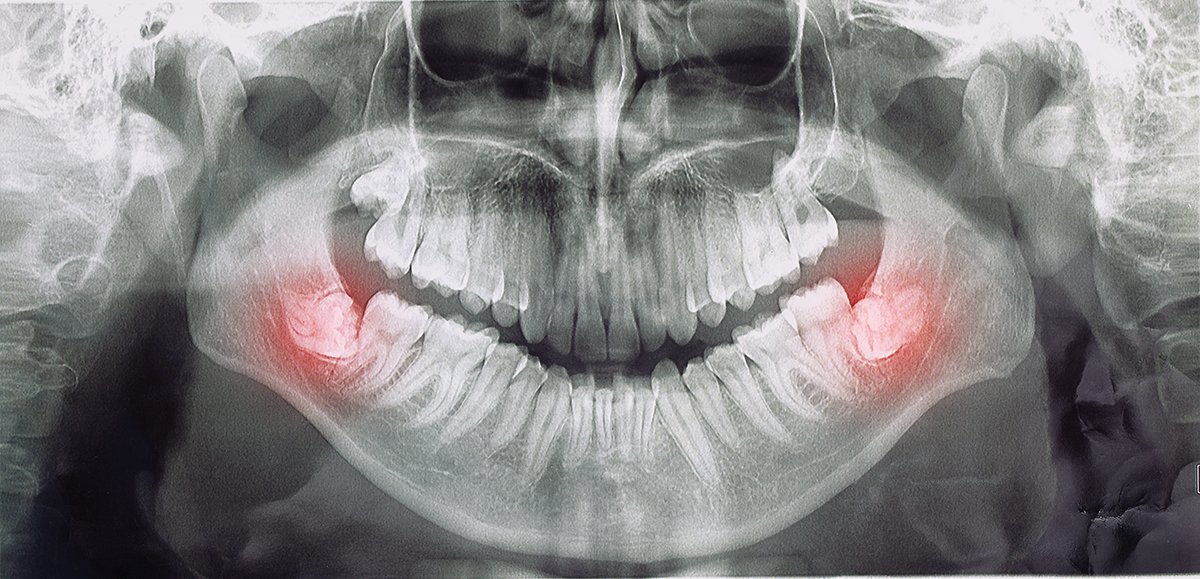

Uno de los casos más comunes es cuando existen caries profundas o fracturas dentales justo bajo el margen de la encía. En estas situaciones, es necesario realizar un alargamiento coronario para acceder al daño, eliminar la caries y permitir una reconstrucción adecuada.

De igual forma, si una corona o restauración debe colocarse muy cerca o debajo de la encía, este procedimiento permite exponer el diente sano y asegurar que la corona quede bien sellada y fija, evitando filtraciones y despegues futuros.

También se recomienda en casos de fracturas dentarias donde se ha perdido estructura dental. La cirugía permite reconstruir el diente de forma segura y funcional, mejorando su retención y durabilidad.